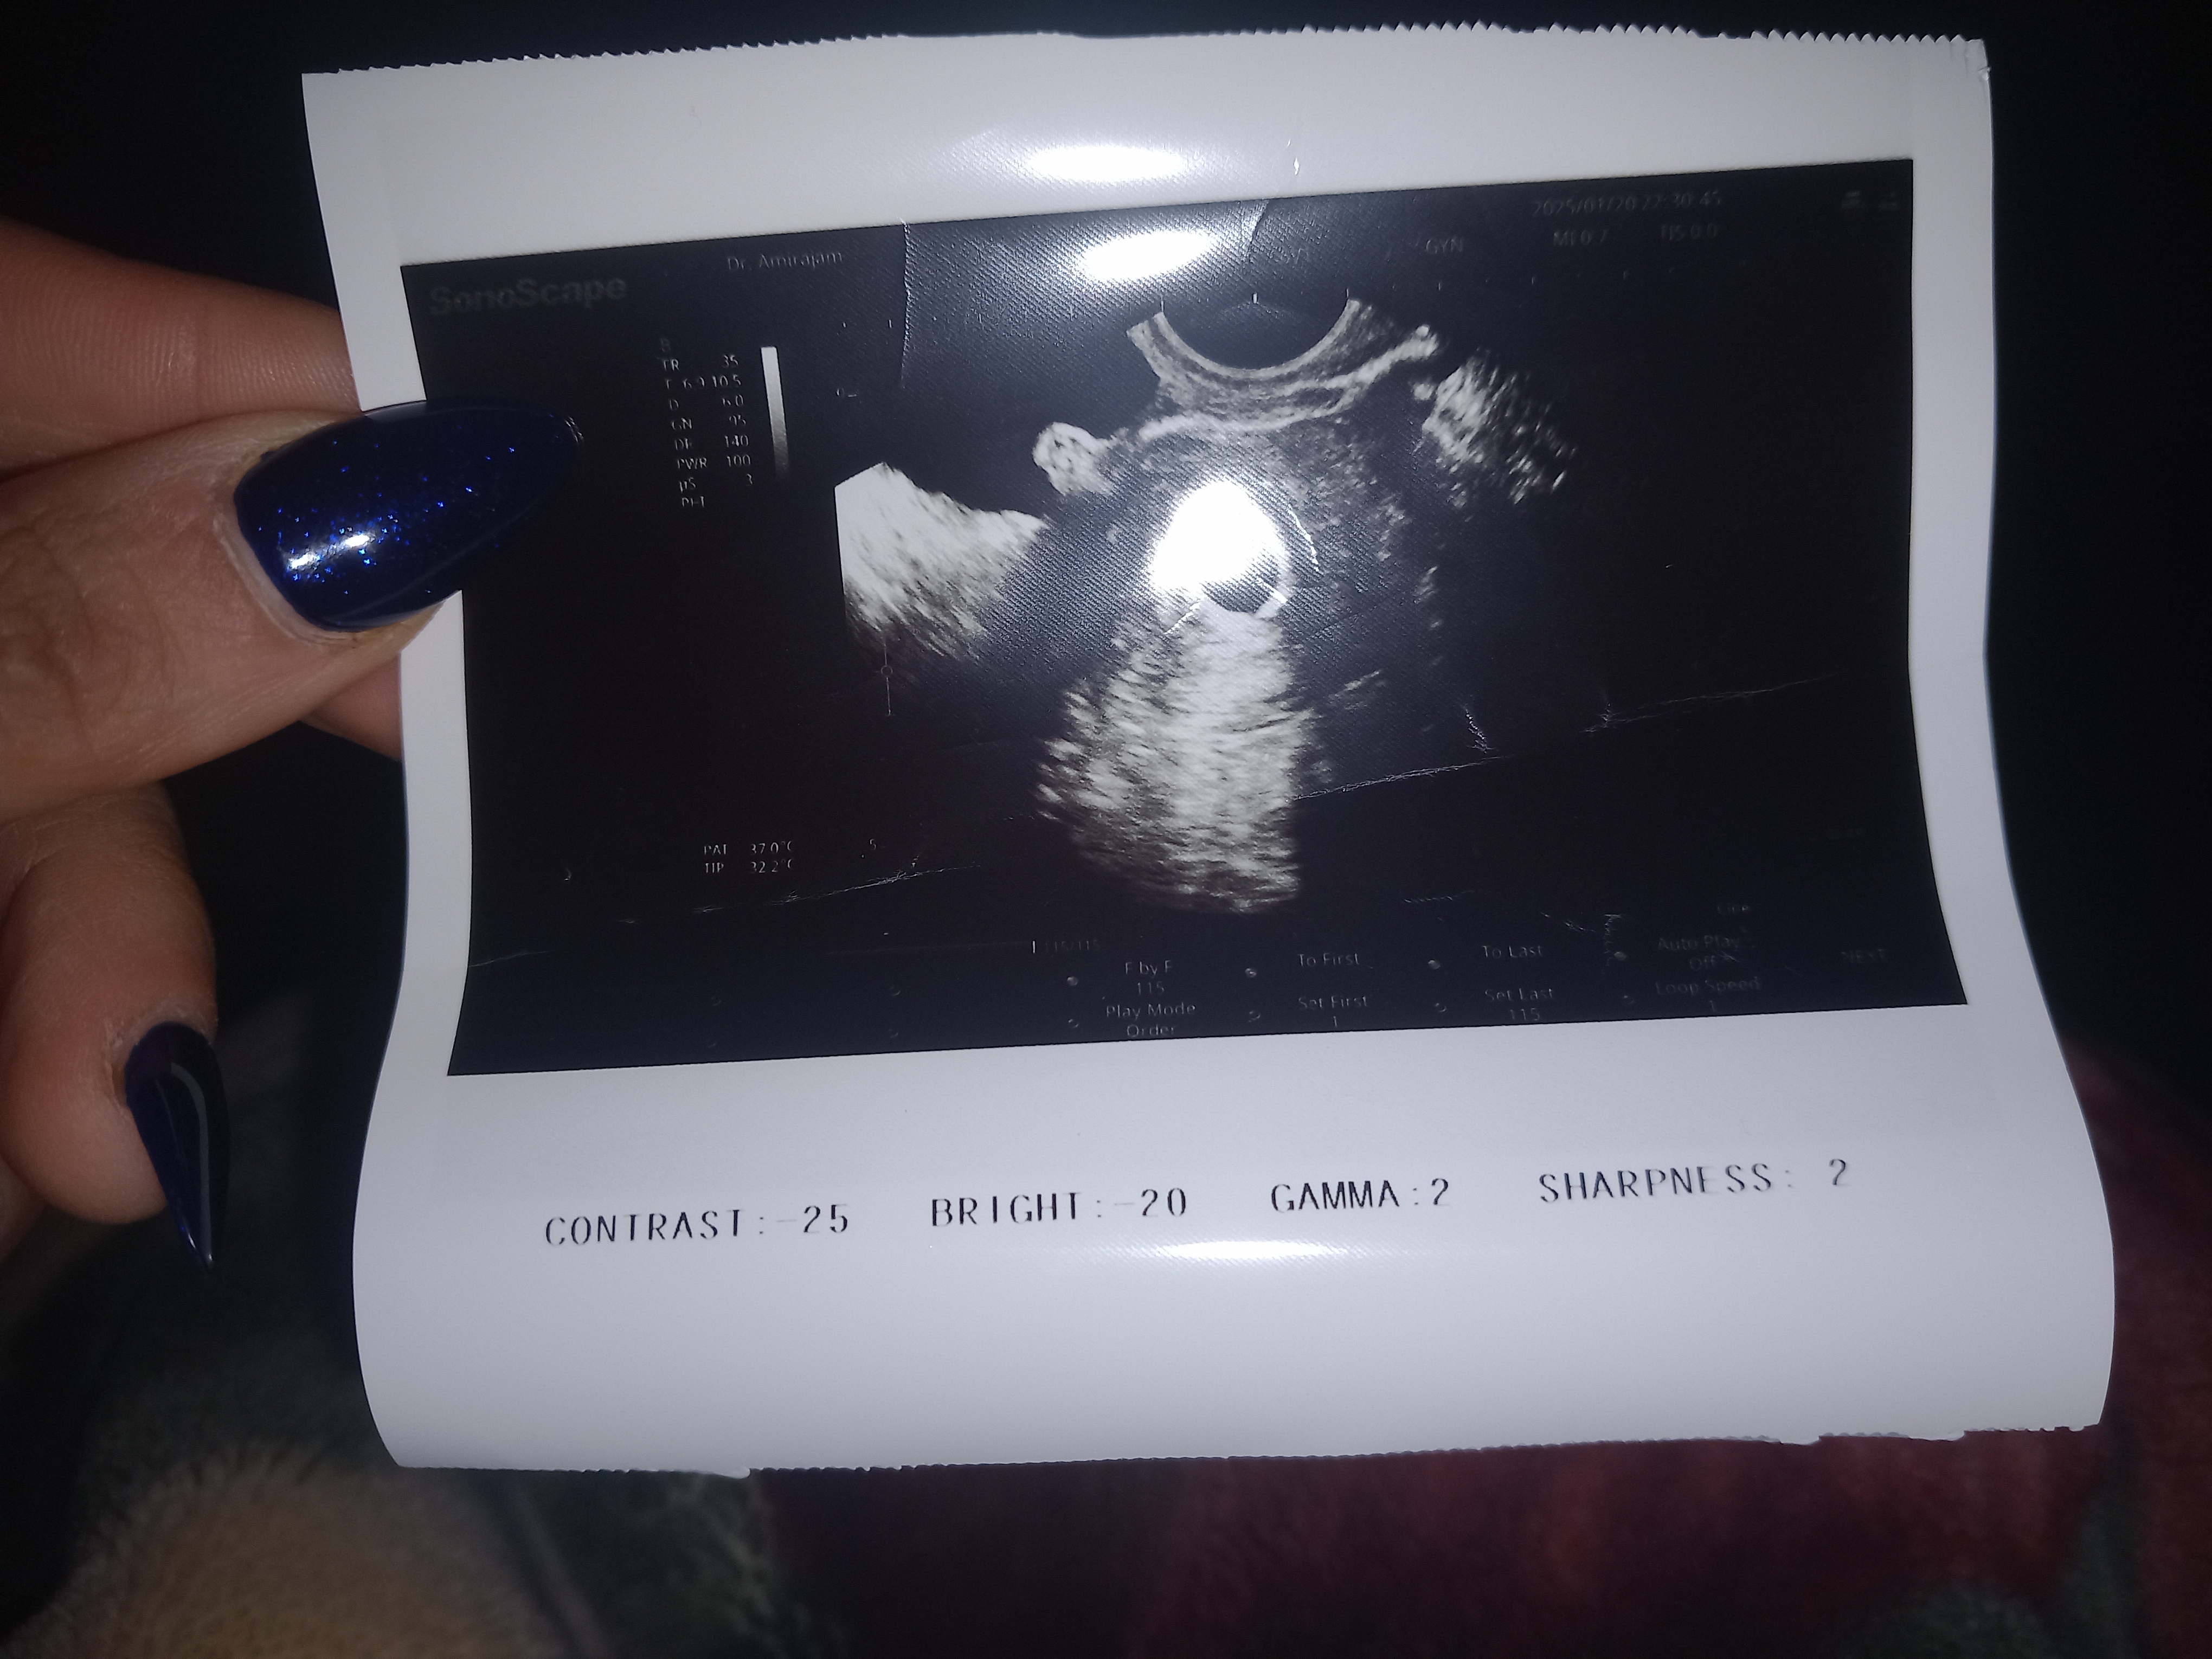

شرح سونو بهت ندادن؟

اونیکه توش قطر ساک و قطب جنینی و کیسه زرده نوشته میشه، البته اون اعداد و اصطلاحات انگلیسی کنار عکس که الان توی تصویر مشخص نیست هم همین چیزاس که گفتن که علائم اختصاری هستن ‌که پزشک به اونها توجه میکنه